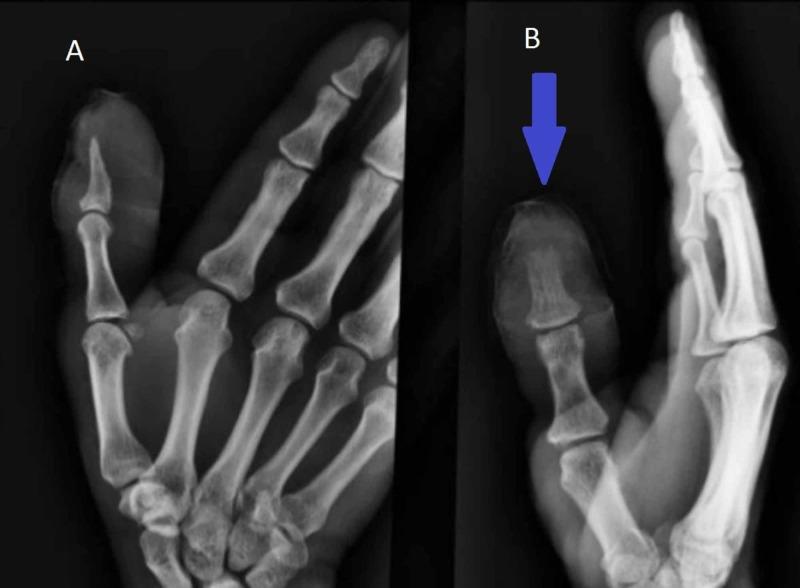

Nocardia is an uncommon gram-positive, weakly acid-fast bacterium that causes systemic or localized suppurative disease in humans and animals. Nocardiosis is typically regarded as an opportunistic infection, but approximately one-third of the patients are immunocompetent. The most common presentation is pulmonary disease (39%) followed by systemic involvement, defined as involvement of more than two sites; cutaneous presentation constitutes only 8% of the cases. Nocardia is widely distributed geographically; however, in the US, it is mostly found in warm and dry areas of South West and South East. We present a perfect case of cutaneous nocardiosis of a 70-year-old male, who presented with a traumatic splinter injury, leading to pustules formation on the right index finger, along with erythema and induration of the right arm. The patient was empirically diagnosed and treated for cellulitis, with amoxicillin and clavulanic acid, resulting in deterioration of the wound. The patient underwent incision and drainage and wound culture grew nocardia. The index of suspicion should be kept in mind while treating infectious blisters which have failed outpatient cellulitis treatment, immunocompromised hosts, and in nocardia prevalent regions.

诺卡菌是一种罕见的革兰氏阳性、弱抗酸菌,可在人和动物中引起全身性或局部化脓性疾病。诺卡菌病通常被视为一种机会性感染,但约三分之一的患者免疫功能正常。最常见的表现是肺部疾病(39%),其次是全身受累,即累及两个以上部位;皮肤表现仅占病例的8%。诺卡菌在地理上分布广泛;然而,在美国,它主要见于西南部和东南部温暖干燥的地区。我们报告一例70岁男性皮肤诺卡菌病的典型病例,该患者因手指外伤后出现右手食指脓疱,伴有右臂红斑和硬结。患者最初被经验性诊断为蜂窝织炎,并使用阿莫西林和克拉维酸进行治疗,结果伤口恶化。患者接受了切开引流,伤口培养出诺卡菌。在治疗门诊蜂窝织炎治疗无效的感染性水疱、免疫功能低下宿主以及诺卡菌流行地区时,应提高警惕。